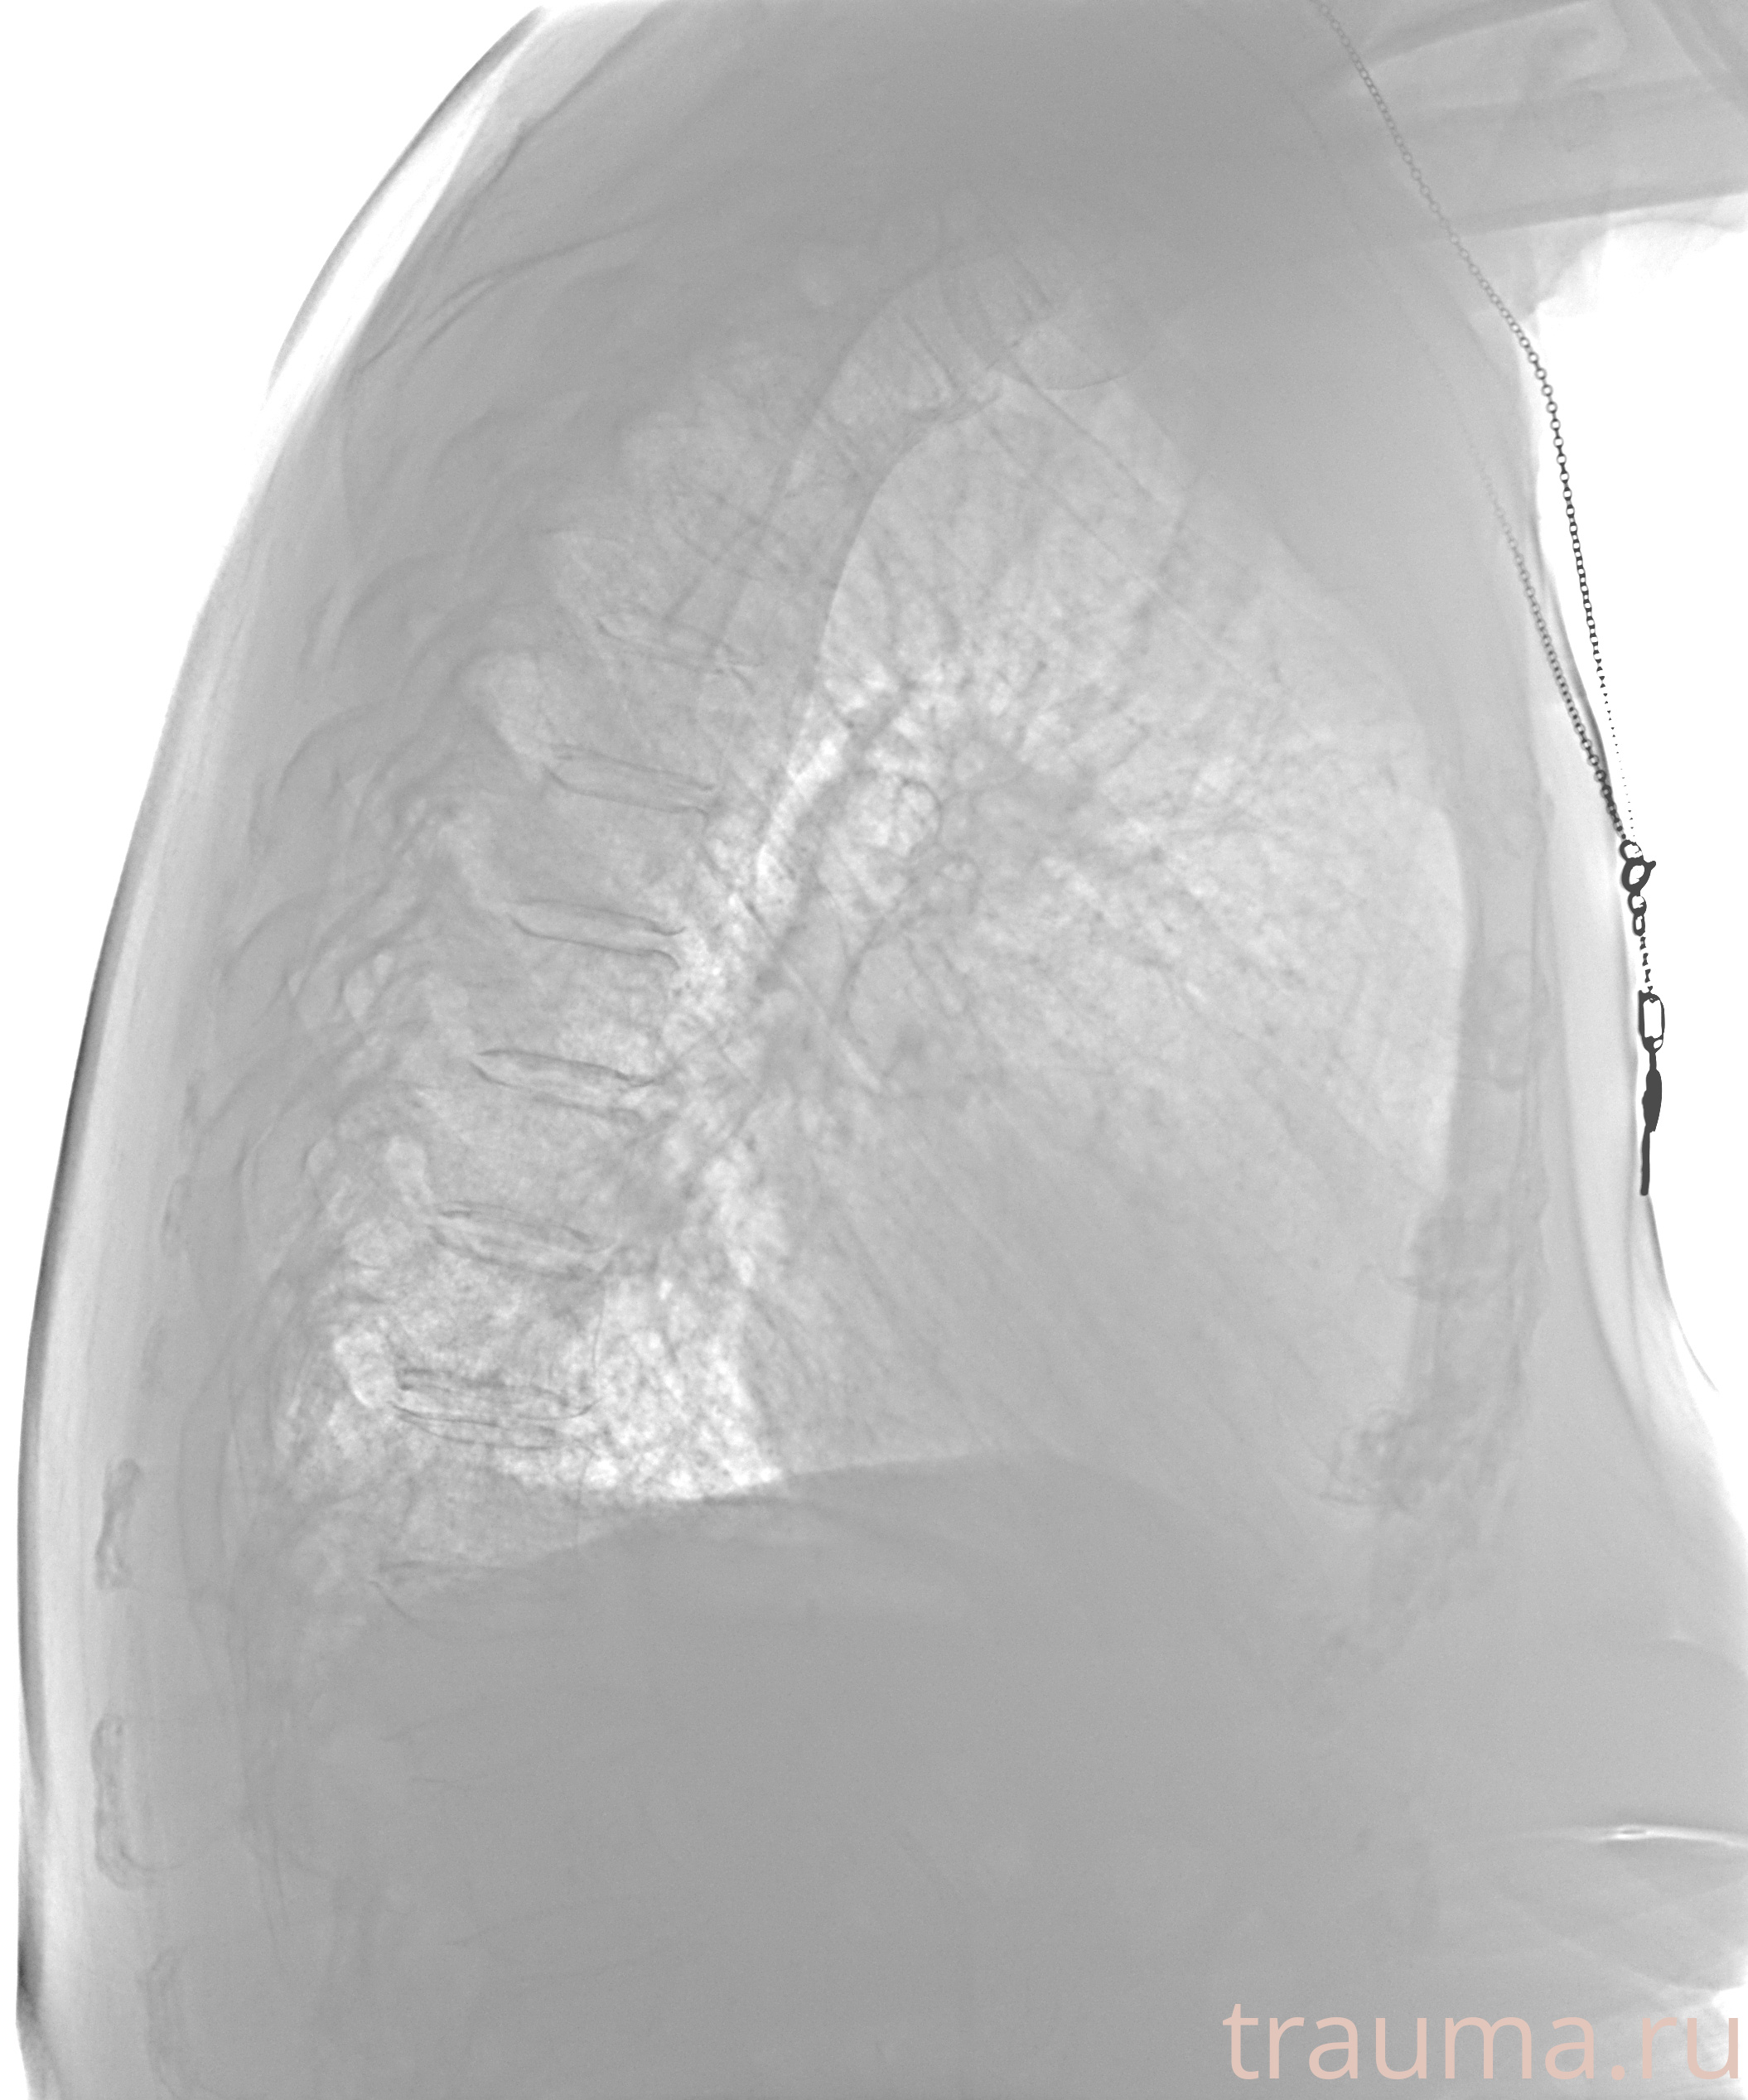

Рентгенограммы

Рентген на дому: по вашему адресу приезжает врач-рентгенолог, травматолог-ортопед с мобильным рентгеновским аппаратом, проводит диагностику травмы или заболевания, делает необходимые рентгенограммы, дает рекомендации по дальнейшему лечению. Получить качественные снимки в домашних условиях возможно благодаря уникальной методике, разработанной МосРентген Центром для института  Склифосовского